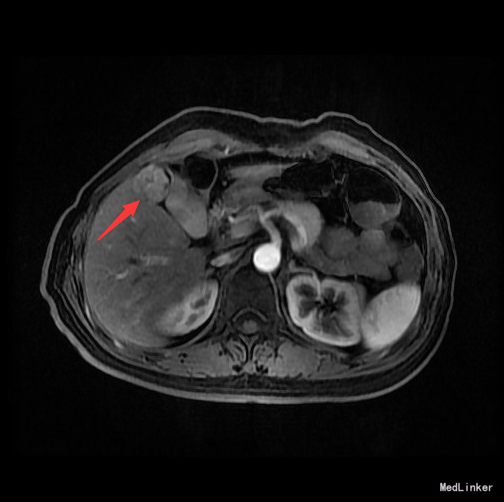

辅查:AFP 3.43ng/ml, CEA 1.47ng/ml。MR:肝S5段占位性病变(26*25mm),考虑肝癌可能性大,建议活检。

随访:术后病理示:(右肝肿物)送检肝组织部分呈结节状增生,结节间见粗细不等的纤维间隔,其内见血管增生,少量淋巴细胞及浆细胞浸润,符合肝局灶性结节状增生(FNH)。 讨论:肝局灶性结节增生(FNH)是肝内第二常见良性肿瘤,一般无临床症状,影像学表现,MRI上T1WI和T2WI与周围肝实质信号相近,增强扫描动脉期明显强化,若存在中央瘢痕,则中央瘢痕不强化,门脉期及静脉期强化程度减退,中央瘢痕则呈延迟强化。FNH需与肝癌和肝腺瘤鉴别,本例即误诊为肝癌,若存在中央瘢痕,则诊断较容易。